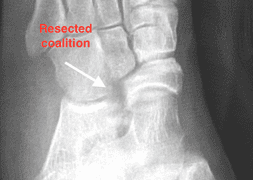

After resection of the coalition the remaining bone is either coated with bone wax or a soft tissue spacer, such as fat or muscle, is placed at the site where the coalition used to be, to prevent recurrence.

Pictured above is a middle facet coalition which was resected through a 2cm incision.

Realignment of the foot can be achieved through bony work with grafting(as pictured above) as well as placement of an arthroreisis.